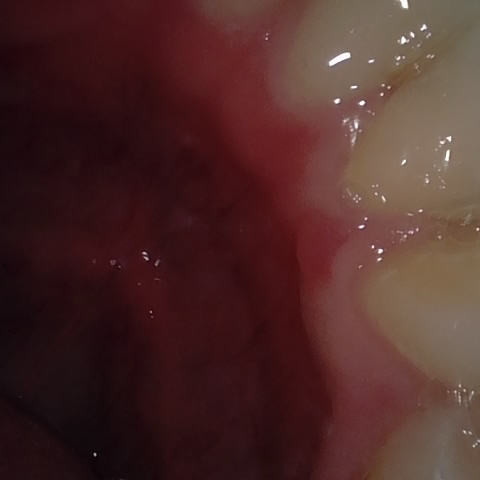

Annotated as "Bad"